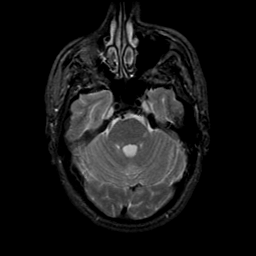

MR Study #9, April 14, 1991 -- Slice #14